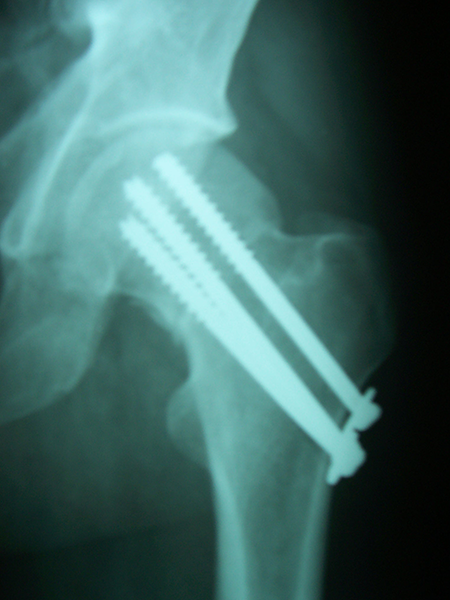

Case:7 Fracture Neck Femur with Implant failure and Re-Fixation with hemi-arthroplasty

Alcoholic Gardener by profession had slipped in bathroom & fell. He sustained fracture neck femur.He was operated with closed reduction & CC Screw fixation under IITV. Two weeks’ post fixation he again fell & sustained fracture in sub trochanteric region. He was treated with Hem-Arthroplasty with Tension band wiring.

Pre-Op

Post-Op